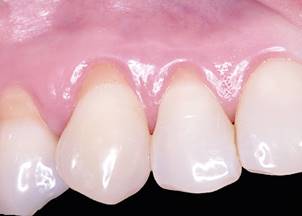

For post-operative care, the patient was instructed to keep a soft diet for 7 days, drink plenty of liquids, and not brush the operated areas for 4 weeks. Follow-up consultations took place at 7, 14, 60, 180 days, and 5 years post-surgery. At 14 days, the tissue adhesive was loose and the dentist removed it. If the product accidentally be swallowed, no side-effects are expected, according to the manufacturer. At 60 days, complete coverage of the recession was achieved. At 5 years, the gingival margins were stable, as clinically assessed (Fig. 3). The PD and CAL were both of 1 mm. (Table 1)